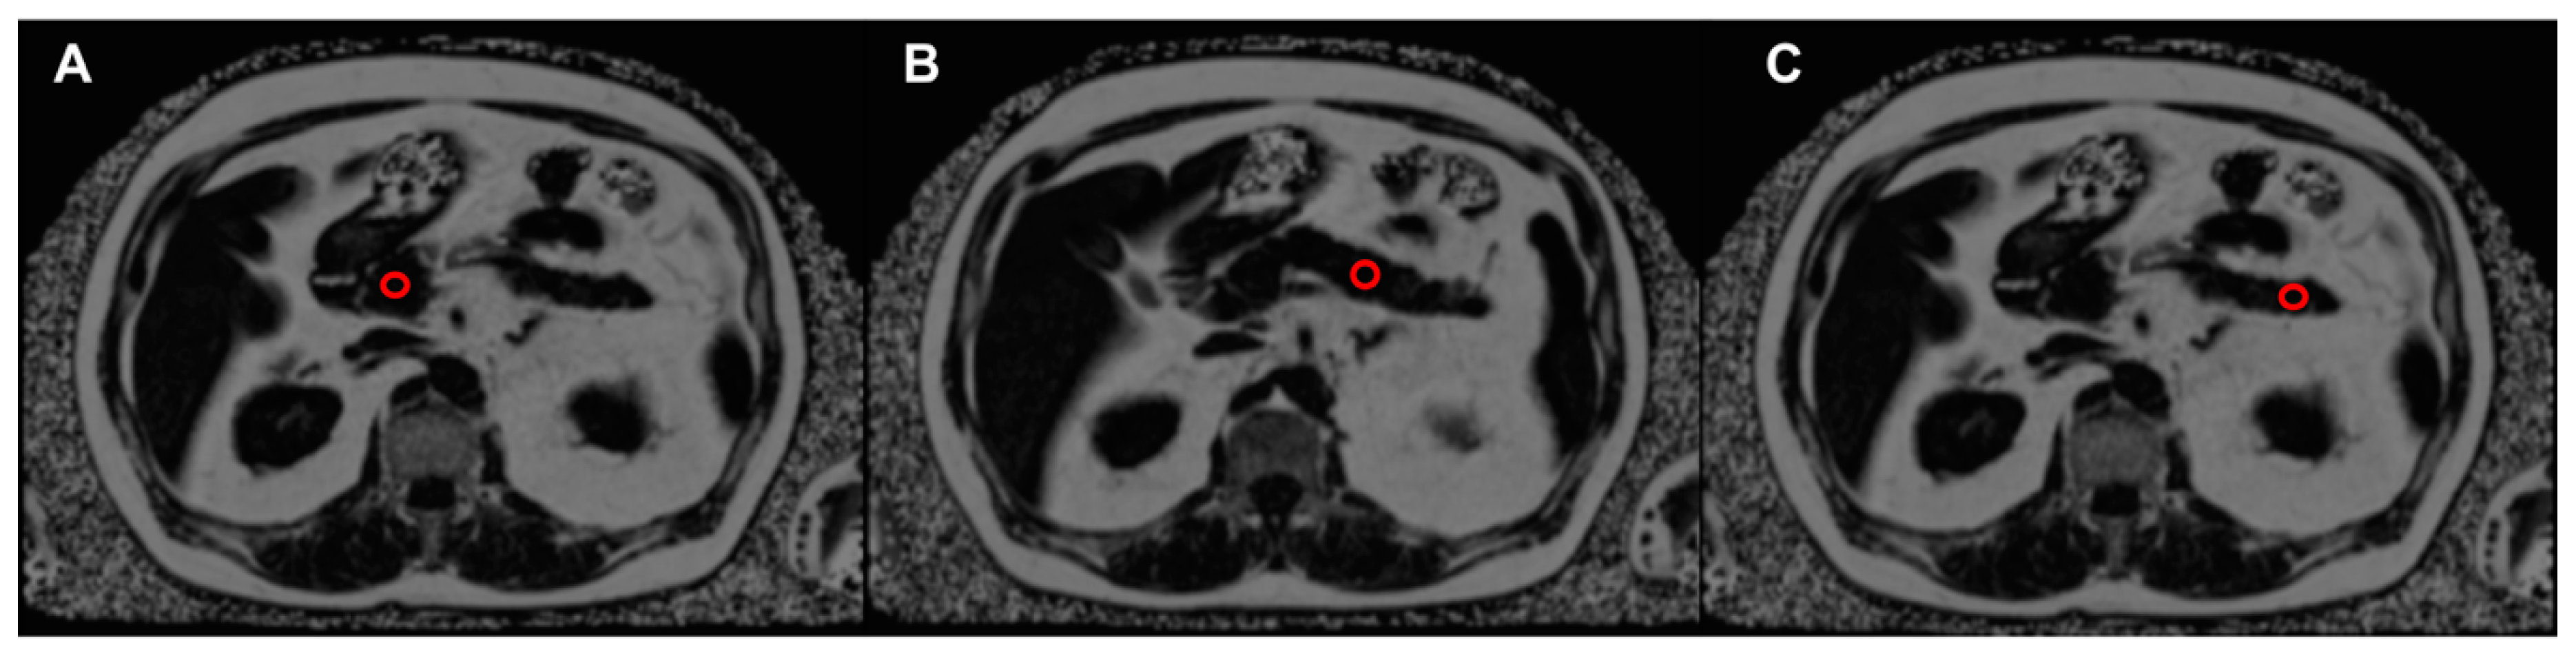

2.3. Imaging